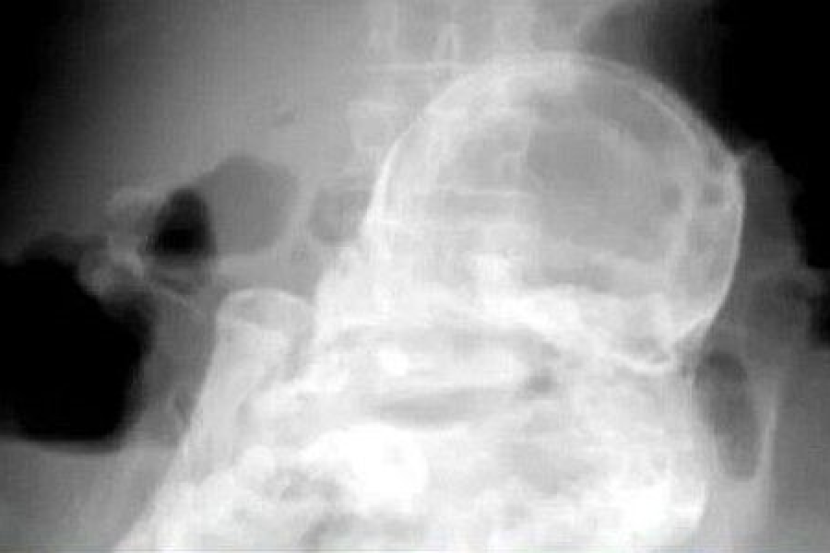

Tocantins, Brazil: Doktor di sini terkejut selepas menemui bayi yang telah mengeras seperti batu di dalam perut seorang wanita berusia 84 tahun.

Sejak itu bayi terbabit dipercayai mengeras di dalam perutnya dan menjadi Foetus.

Foetus itu dikesan oleh doktor selepas melakukan imbasan x terhadap warga emas berkenaan yang mendakwa mengalami kesakitan di dalam perut.